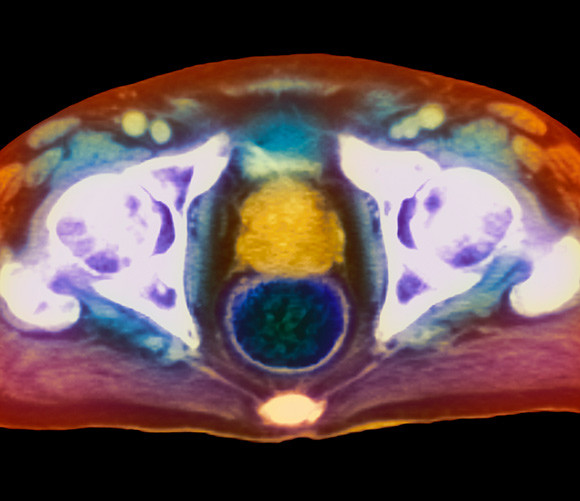

MR-undersøkelse av et aksialt (horisontalt) snitt gjennom en manns bekken viser kreft i prostatakjertelen (gult). Foto:…

MR-undersøkelse av et aksialt (horisontalt) snitt gjennom en manns bekken viser kreft i prostatakjertelen (gult). Foto: Science Photo Library